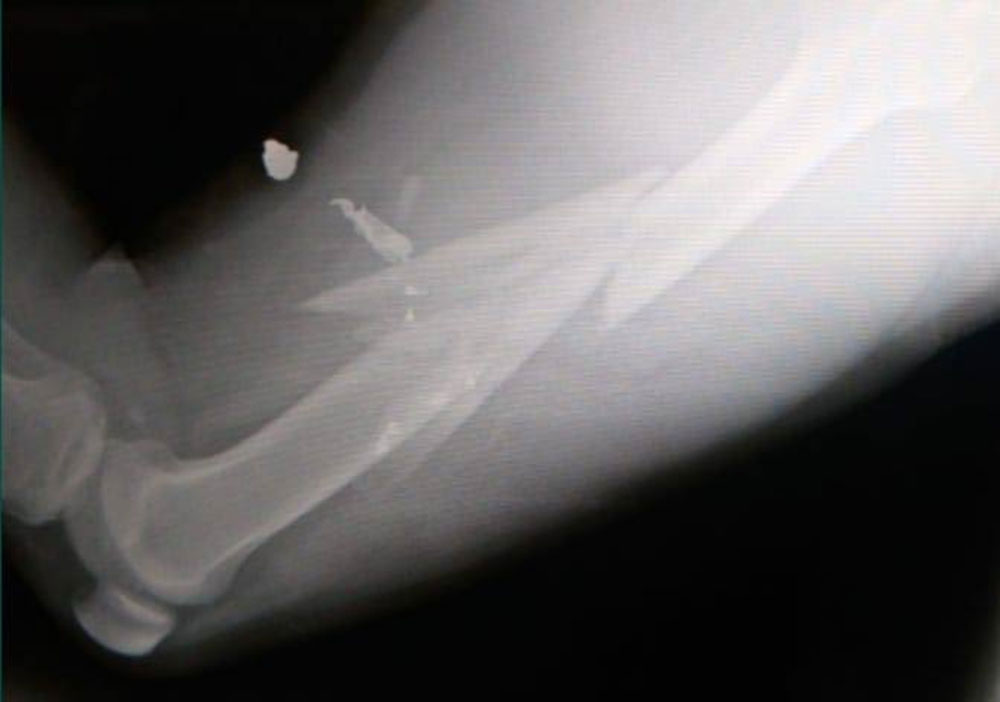

Luego en el mismo comunicado se adjunta imágenes de la herida y radiografía de la zona de la lesión de la víctima, precisando que “el compañero se encuentra internado aún con la bala alojada en la pierna a la espera de ser operado. Este caso no es un hecho aislado sino que es parte de la violencia institucional que registra un aumento de las detenciones arbitrarias y el gatillo fácil en el marco de la cuarentena”.

Un médico policial en turno diagnosticó que el herido presentaba “fractura de fémur izquierdo, producto de proyectil de arma de fuego, con tiempo de curación de unos 40 días, de no mediar complicaciones”.